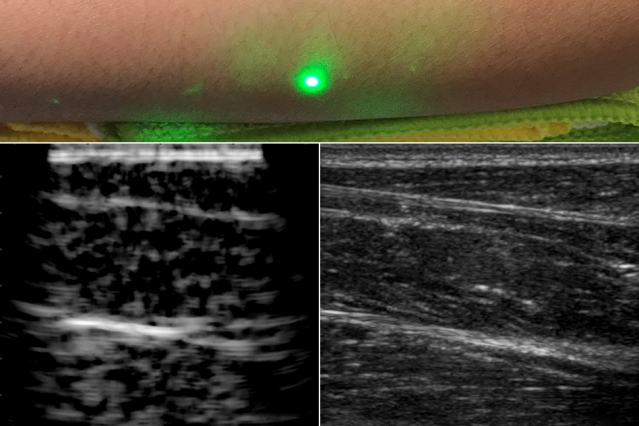

MIT공대 연구팀이 레이저를 이용한 비접촉식 초음파 검사 시스템 개발에 성공했다. 인체를 화상화하는 기술 중에서도 초음파 검사는 엑스선 촬영, CT 검사가 ...